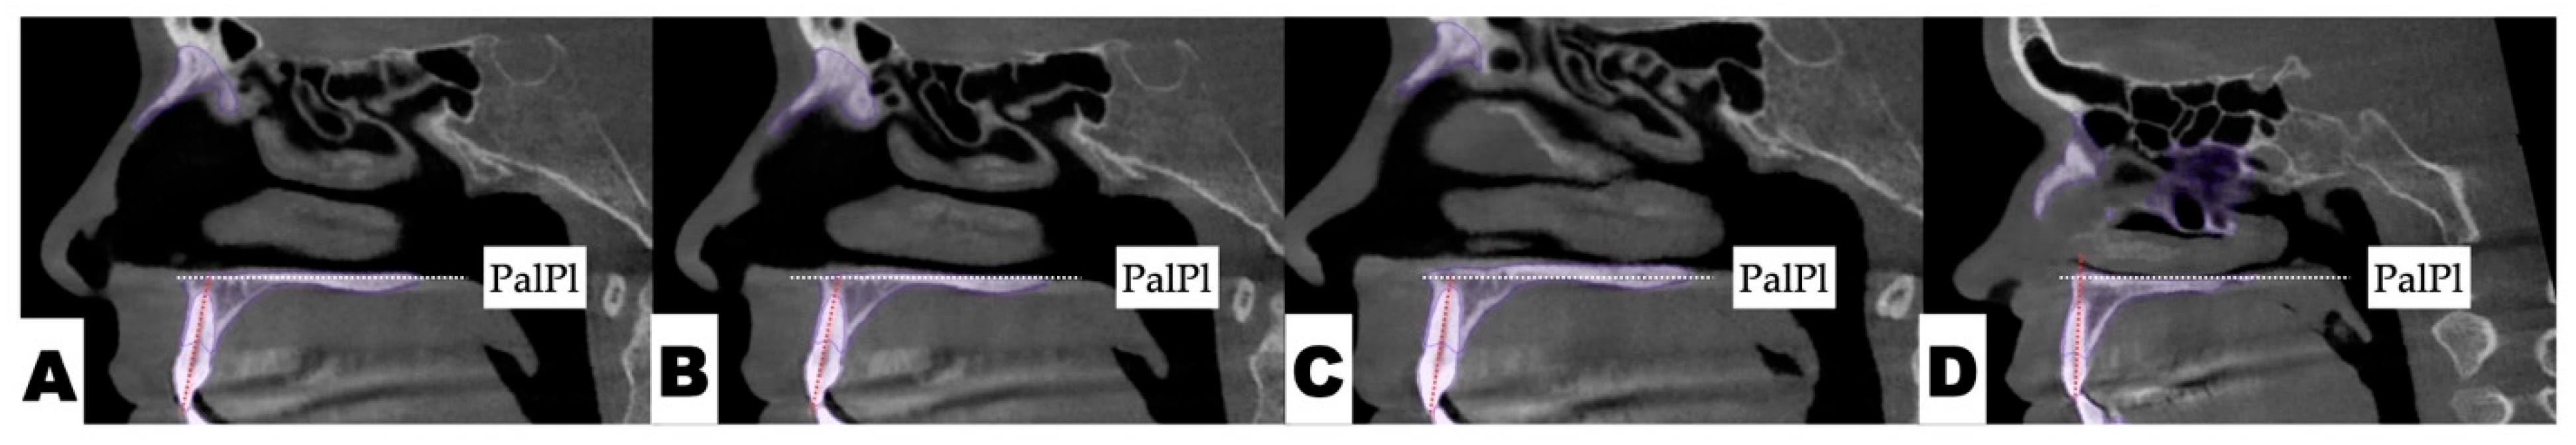

2.3.1. Surgical Protocol

2.3.2. Design of 3D Surgical Guide

2.3.3. Osteotomy Planning and Appliance Design